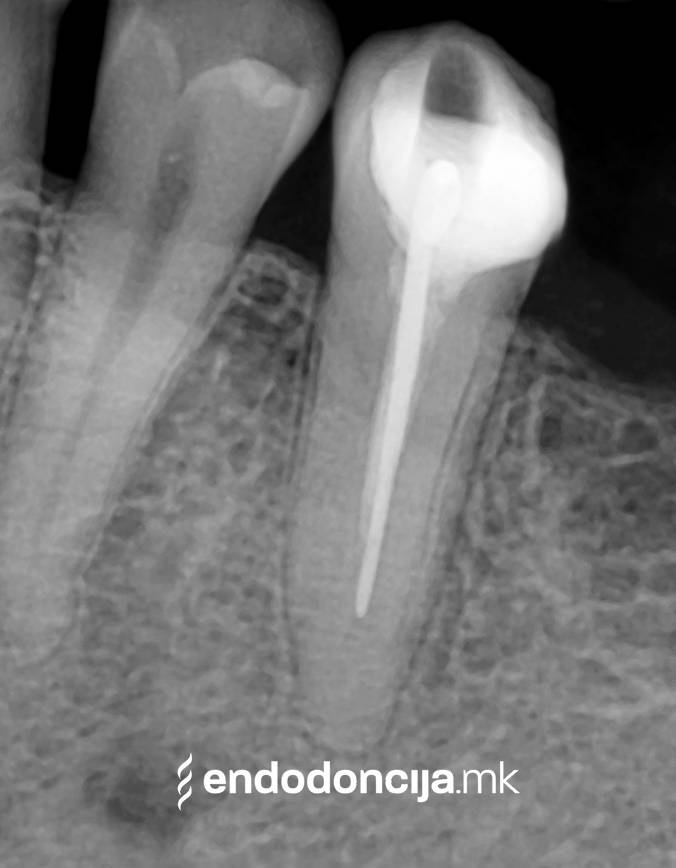

Στο Ειδικό Τμήμα Ενδοδοντικής, αντιμετωπίζουμε τους ασθενείς μας στο υψηλότερο επαγγελματικό και διαγνωστικό επίπεδο. Οι μονάδες θεραπείας μας είναι εξοπλισμένες με τα πιο σύγχρονα χειρουργικά μικροσκόπια, τα οποία υποστηρίζουν μια λεπτομερή αναπαράσταση και προετοιμασία ρίζας και προσφέρουν ένα εντελώς νέο επίπεδο ακρίβειας. Ο νεότερος ενδοδοντικός εξοπλισμός, όργανα και υλικά πλήρωσης χρησιμοποιούνται. Με αυτόν τον τρόπο μπορούμε να διατηρήσουμε τη θεραπεία όσο το δυνατόν συντομότερη, ακόμη και σε περίπλοκες περιπτώσεις, και να αποφύγουμε την απώλεια δοντιών.

Εκτός από την ανίχνευση των ριζικών καναλιών, η ενδελεχής προετοιμασία και η απολύμανση του ριζικού σωλήνα είναι η προϋπόθεση για μια επιτυχημένη συνολική θεραπεία. Μέσω της χρήσης των νεότερων οργάνων και αντιβακτηριακών διαλυμάτων, όλα τα υπολείμματα ιστών και τα βακτήρια που υπάρχουν μπορούν να εξαλειφθούν.

Κατά τη διάρκεια της επεξεργασίας του ριζικού σωλήνα, τα λεπτά όργανα ενδέχεται να σπάσουν. Αυτό μπορεί να αποτελέσει εμπόδιο για την πλήρη προετοιμασία και τον καθαρισμό του ριζικού σωλήνα. Με μια μικροσκοπική επεξεργασία του ριζικού σωλήνα μπορεί να είναι δυνατή η απομάκρυνσή τους υπό ορισμένες συνθήκες, χωρίς να καταστρέφεται η ουσία των δοντιών.

Κατά τη διάρκεια προηγούμενων θεραπειών, το δόντι μπορεί όχι μόνο να έχει αποδυναμωθεί από τη μηχανική επεξεργασία του ριζικού σωλήνα αλλά και από τη στερέωση και την αγκύρωση ενός ρίζα. Όταν αναθεωρείται η επεξεργασία ενός ριζικού καναλιού, αυτοί οι πείροι πρέπει να αφαιρούνται όσο το δυνατόν πιο προσεκτικά για να διατηρούν σημαντική ουσία των δοντιών.

Οι υπηρεσίες του Ειδικού Τμήματος Ενδοδοντικής δεν περιορίζονται καθόλου στη συμβατική επεξεργασία ριζικών καναλιών. Αντιμετωπίζουμε αποκλειστικά τους ασθενείς μας με τα νεότερα υλικά και όργανα με μικροσκόπιο, προκειμένου να είμαστε σε θέση να καθαρίσουμε εντελώς και να προετοιμάσουμε όλα τα κανάλια πριν τα γεμίσουμε.